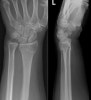

X-ray : 콜레스골절(Colle’s fracture)

1. 콜레스 골절(Colles fracture) : 요골 먼쪽의 골절 부분이 위쪽 또는 뒤쪽으로 전위되는 유형으로 가장 흔합니다. 관절면이 같이 골절되기도 하고 척골 경상돌기의 골절도 흔히 동반됩니다. 최근에는 골다공증이 많아지고, 심하지 않은 통증으로도 병원을 찾는 예가 많아 미세한 골절을 종종 보게 됩니다.